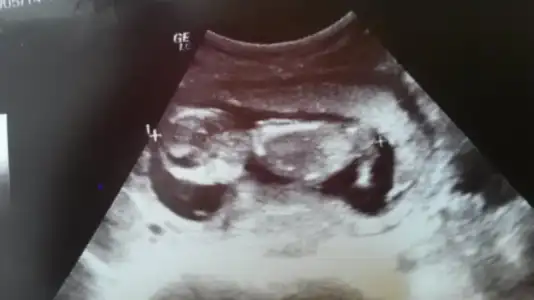

dr soylemeden siz gorun genital nub teorisi ( bebegin cinsiyeti)

c.tesi günü gittik doktora 11+5 günlüktük. Daha 7.haftada zıp zıp top gibi oynuyordu

cteside felaket derecede hareketliydi geri doğru takla atıyordu o anda doktor iyice baktı

ultrasonu dondurup arada bi çıkıntı var gibi ama kızlarda da oluyo sanki biraz daha erkeğe benziyo dedi

alışveriş yapma bekle 1 ay sonra netleştiririz dedi bende netten diğer ultrason resimlerine bakıyorum

kız bebeklere benziyor benimkide bakalım hayırlısı inşallah dediğin gibi kızdır:)

merve birde neresi benziyor "nub" neresi oluyor?

orda paralel bişeyler var ama tam anlayamadım bende :44:

Benimki de tabi tahmin ama ben kırmızı çerçeve içine aldığım çıkıntı diye düşündüm :) Şu an kaçıncı haftadasın doktor tahmin yürütmedi değil mi hiç? Bizimki de bir şey demedi biz de sormayı unutmuşuz :) 7 haziranda öğreneceğiz.

bizimki çok hareketli görünmüyor dedi ben ısrar edince erkeğe biraz daha fazla benziyo sanki çıkıntı var gibi ama kızlarda da oluyo dedi

o işaretlediğin yerdeki ve onun hemen altındaki de paralel yukarı doğru bişey göremedim ama nub dan anlayan diğer arkadaşlar daha iyi bilirler tabi :106: